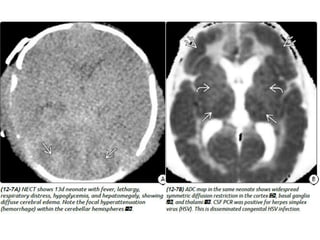

Herpes Simplex Virus

Imaging

Unlike childhood or adult HSE, neonatal HSV CNS infection is much

more diffuse. Both gray and white matter are affected.

Consider neonatal HSV encephalitis when cranial imaging at 2-3 weeks of

neonatal life

shows unexplained diffuse cerebral edema, with leptomeningeal

enhancement, without or with cerebral parenchymal hemorrhage.

Herpes Simplex Virus Imaging Unlikechildhood or adult HSE, neonatal HSV CNS infection is much more diffuse. Both gray and white matter are affected. Consider neonatal HSV encephalitis when cranial imaging at 2-3 weeks of neonatal life shows unexplained diffuse cerebral edema, with leptomeningeal enhancement, without or with cerebral parenchymal hemorrhage.